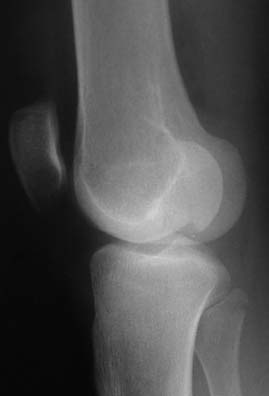

По одной проекции конечно сложно представить себе ситуацию во всех подробностях. Но первое, что приходит в голову, учитывая молодой возраст, хорошую функцию сустава и достаточно ровную линию перелома - открытая репозиция с фиксацией отломков мощными компрессирующими винтами.

“Перелом наружного мыщелка правого бедра во фрональной плоскости был не замечен”

Диагностическая ошибка происходит, когда игнорируется правила обследования внутрисуставных переломов. Вместо полного обследования, включая КТ, ограничиваются рентгенограммой, и то в одной проекции!

Nork et al, J Orthop Trauma, 87:564, 2005 доложили, что над- и чрезмыщелковые переломы бедра в 38% имеют линию перелома в корональной плоскости!